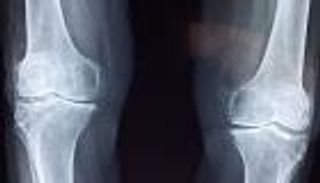

وأشار البروفيسور كلادني إلى أنه من السهل حاليا معرفة ما إذا كان هناك انزلاق غضروفي أم لا، وذلك من خلال الاعتماد على التصوير بالرنين المغناطيسي أو التصوير المقطعي الحاسوبي، وترتبط طريقة علاج الانزلاق الغضروفي بطبيعة أعراض كل حالة مرضية.